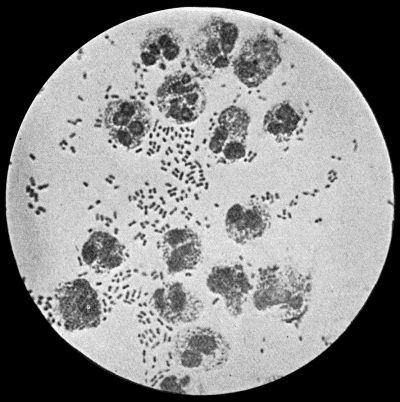

Fig. 2.—Staphylococcus aureus in Pus from case of Osteomyelitis. × 1000 diam. Gram's stain.

Staphylococcus Aureus.—This is the commonest organism found in localised inflammatory and suppurative conditions. It varies greatly in its virulence, and is found in such widely different conditions as skin pustules, boils, carbuncles, and some acute inflammations of bone. As seen by the microscope it occurs in grape-like clusters, fission of the individual cells taking place irregularly (Fig. 2). When grown in artificial media, the colonies assume an orange-yellow colour—hence the name aureus. It is of high vitality and resists more prolonged exposure to high temperatures than most non-sporing bacteria. It is capable of lying latent in the tissues for long periods, for example, in the marrow of long bones, and of again becoming active and causing a fresh outbreak of suppuration. This organism is widely distributed: it is found on the skin, in the mouth, and in other situations in the body, and as it is present in the dust of the air and on all objects upon which dust has settled, it is a continual source of infection unless means are taken to exclude it from wounds.